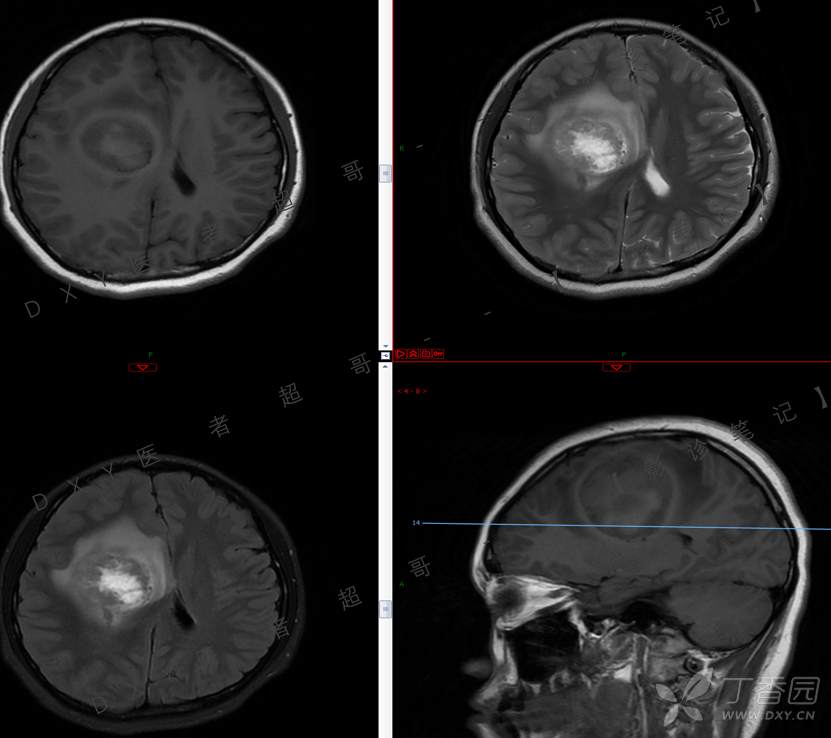

15岁少年,头痛10天,加重伴恶心、呕吐2天,究竟为何?回帖即可查阅病理。

主 诉:头痛10天,加重伴恶心、呕吐2天。

现病史:患者10天前无明显诱因出现头痛,间断发作,无恶心、呕吐,无肢体抽搐等,于当地医院就诊,体温37.4度,予以对症治疗,具体不详,后症状缓解,2天前患者上述症状较前加重,并感双眼胀痛及视物模糊,伴恶心、呕吐,呕吐数次,为胃内容物,再次于当地医院就诊,行颅脑CT考虑“右侧额顶叶病变”,现为求进一步治疗来我院急诊就诊,以“脑脓肿?”收入我科。患者病来精神差,饮食、睡眠欠佳,体重无明显变化。